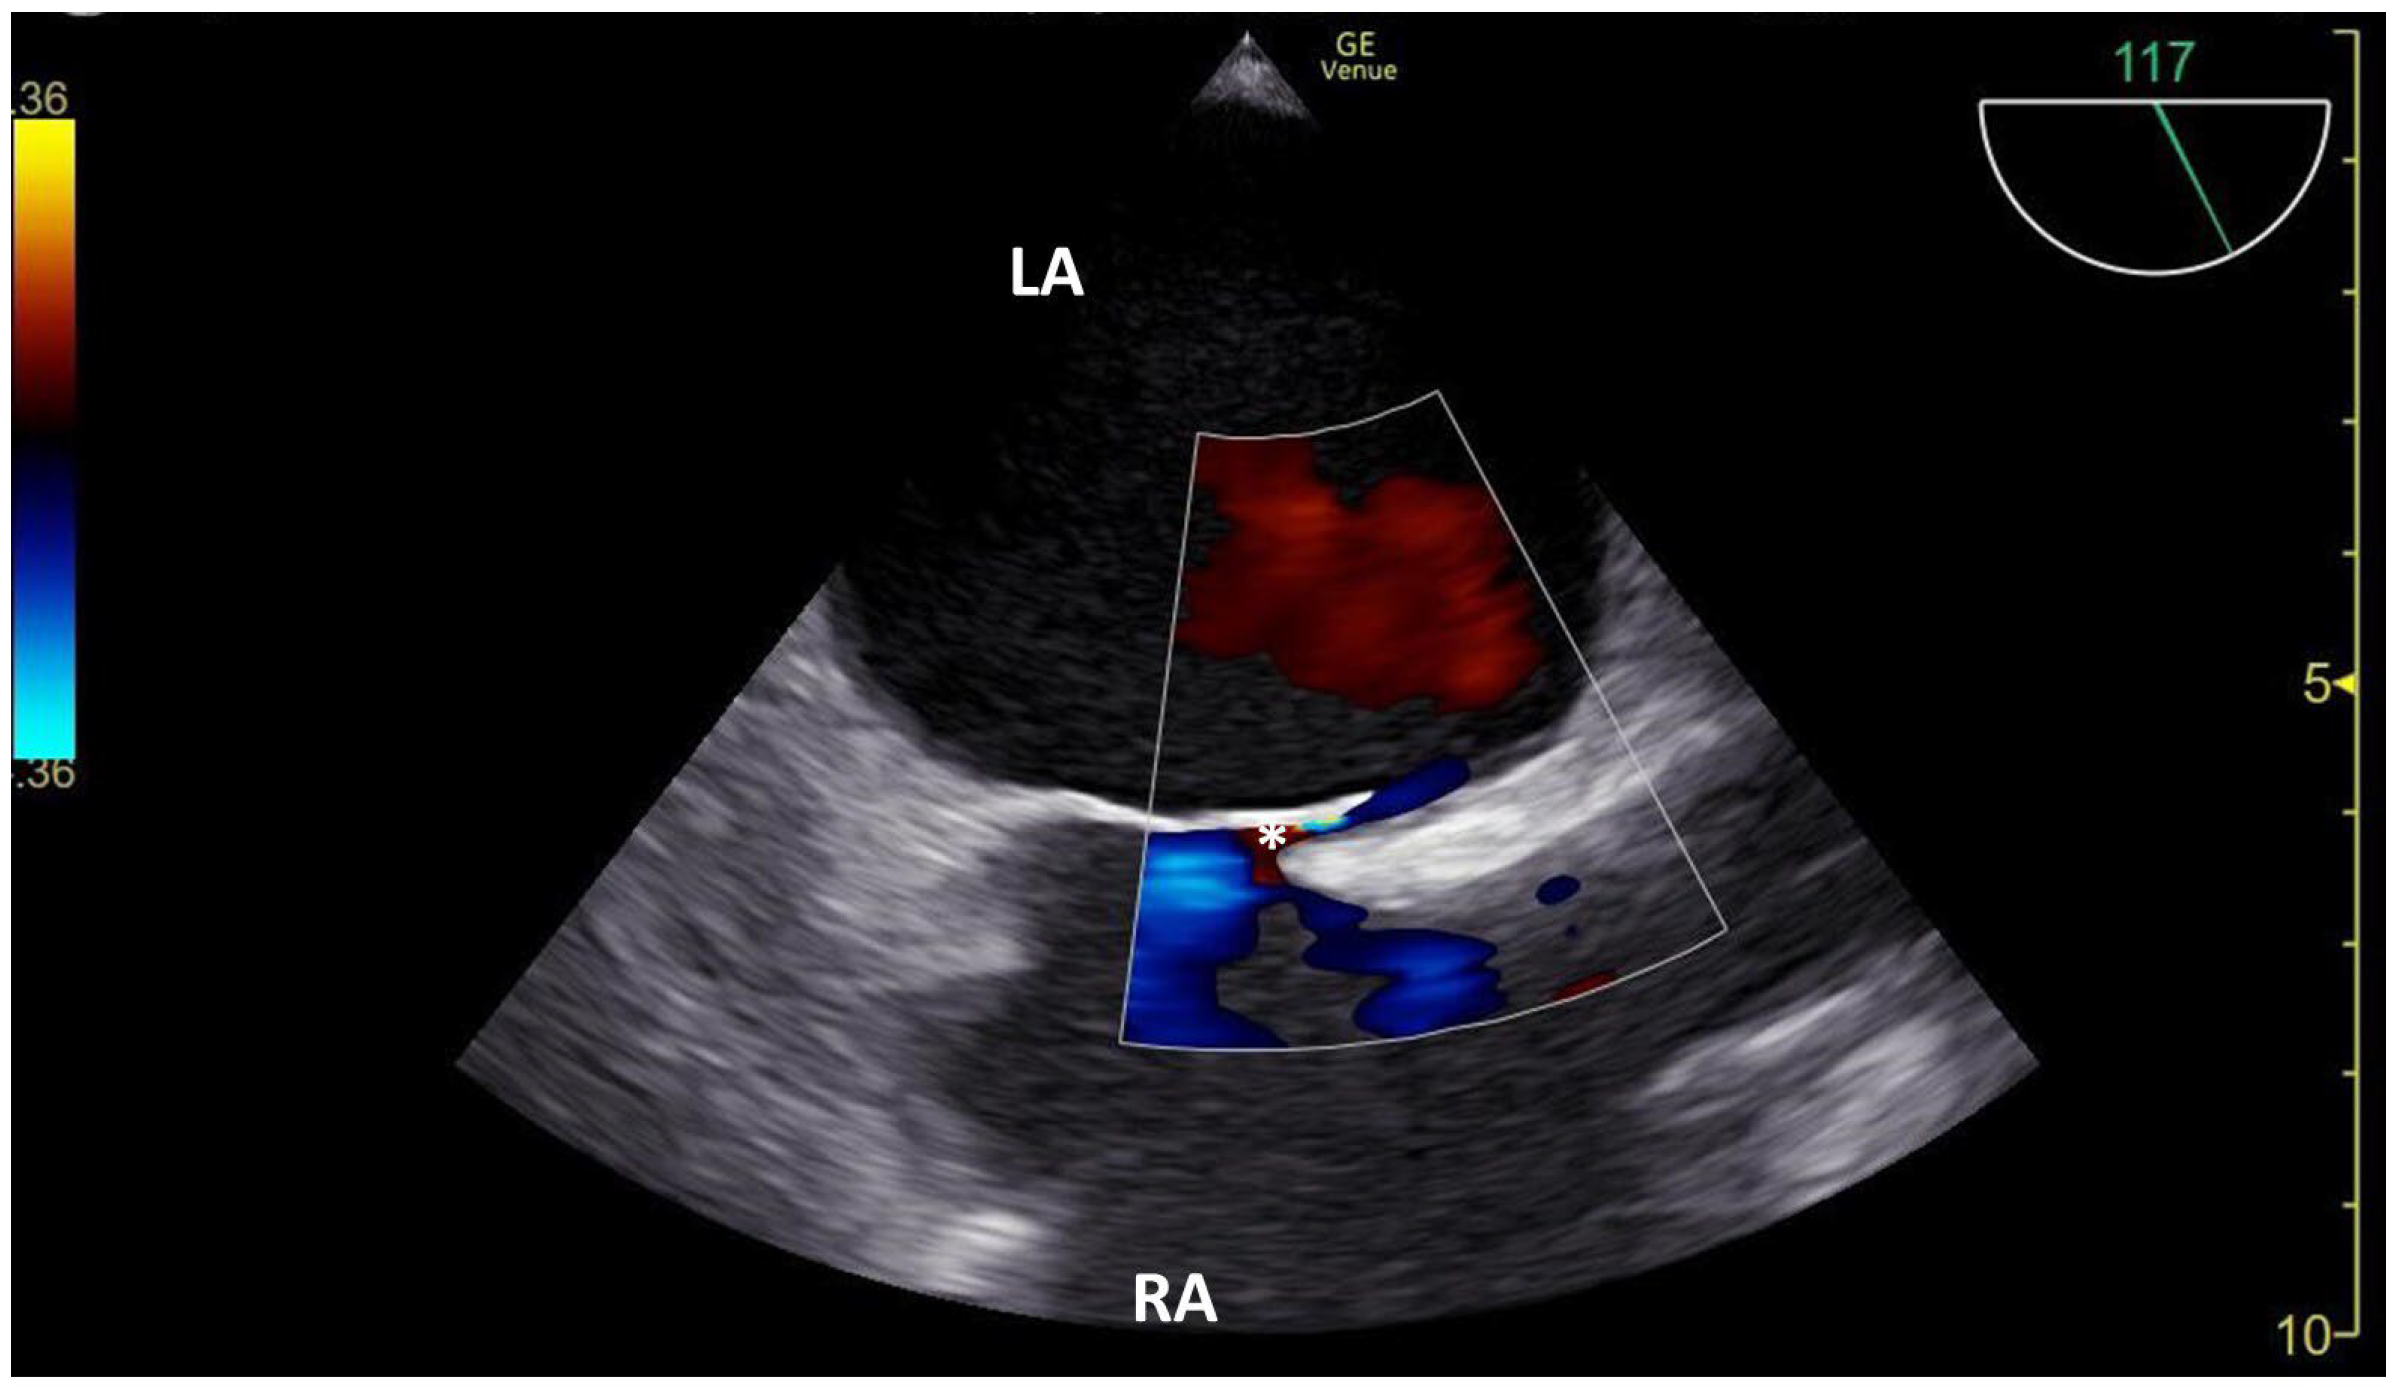

3.1. TCCD MES-Positive Case 1

3.2. TCCD MES-Positive Case 2

3.3. TCCD MES-Positive Case 3